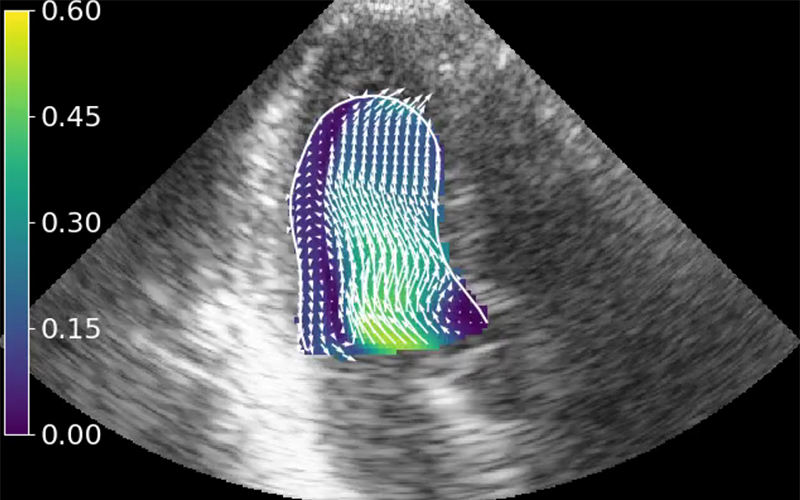

Veocor has developed the first cloud-based tool to diagnose the risk of cardiac thrombus formation and associated stroke. Veocor’s AI-powered technology quickly analyzes standard ultrasound images to provide a measure of blood flow in the left ventricle and identify regions at risk of thrombus formation. No additional hardware or training is required: cardiologists will be able to risk-stratify patients and identify who would benefit from anticoagulation.